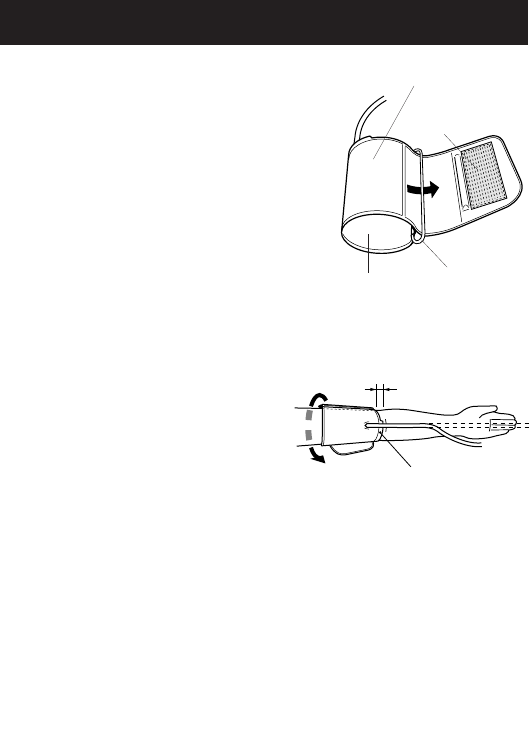

HOW TO APPLY THE ARM CUFF

1. If the cuff is assembled correctly, the sewn

hook material will be on the outside

of the cuff loop and the metal D-ring

will not touch your skin.

2. Pass the end of the cuff furthest from

the tubing through the metal D-ring to

form a loop. The smooth cloth should

be on the inside of the cuff loop.

3. Put your left arm through the cuff loop.

The bottom of the cuff should be

approximately 1/2 inch above the

elbow. The cuff tab on the cuff

should lie over the brachial

artery on the inside of the arm.

The cuff tube should run down

center of arm even with middle finger.

Pile Material

Cuff tab

1/2 inch (12.7 mm)

D-Ring

Smooth Cloth

Sewn Hook

Material